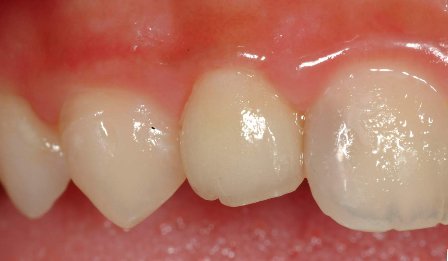

根管內稍做修形後放入玻璃纖維釘柱 , 修形為全瓷冠需要的牙齒形狀後(見圖三),再以雙線排齦方式排齦後印模 , 並以數位照相及電腦比色機比色. 一週後 , 於診間試戴無誤後 , 以永久黏著劑黏上 . 美觀與自然程度符合病人的需求 . 外形如圖四所示

圖三 |